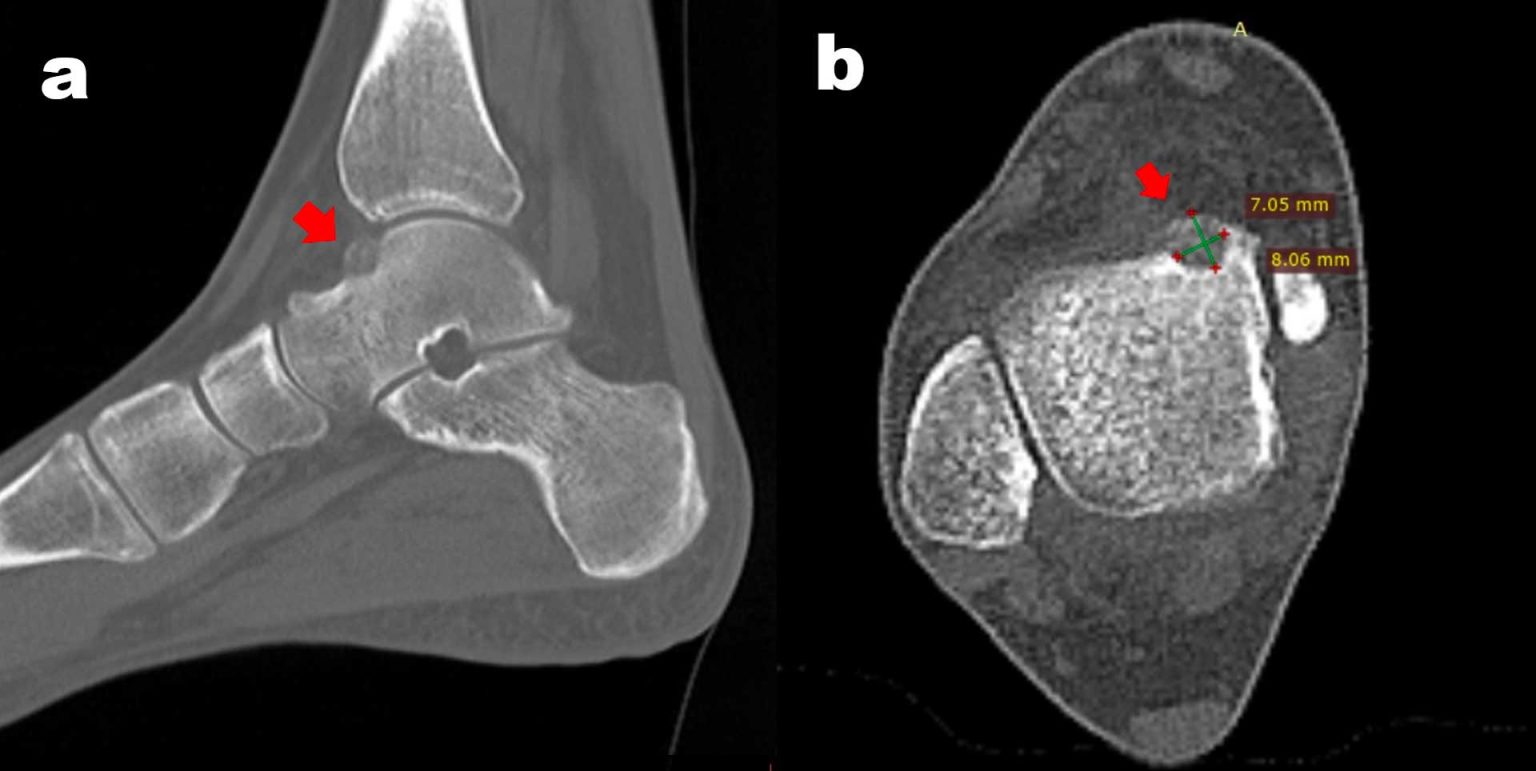

CT of an osteoid osteoma of the talar neck with typical perifocal Talar Neck Bone Marrow Edema When the acl is torn, the bones suddenly shift, causing a. Your doctor may call it bone marrow lesions. Bone marrow edema may present in a few hindfoot bones simultaneously or in a single bone. Bone marrow edema is when fluid builds up in your bone marrow. Bone marrow edema syndrome of the foot and ankle, also known as transient. Talar Neck Bone Marrow Edema.